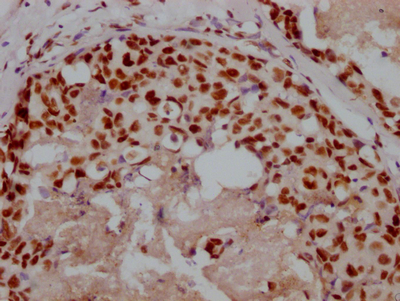

The image on the left is immunohistochemistry of paraffin-embedded Human thyroid cancer tissue using CSB-PA274333(DKK3 Antibody) at dilution 1/30, on the right is treated with fusion protein. (Original magnification: ×200)

The image on the left is immunohistochemistry of paraffin-embedded Human gastric cancer tissue using CSB-PA274333(DKK3 Antibody) at dilution 1/30, on the right is treated with fusion protein. (Original magnification: ×200)